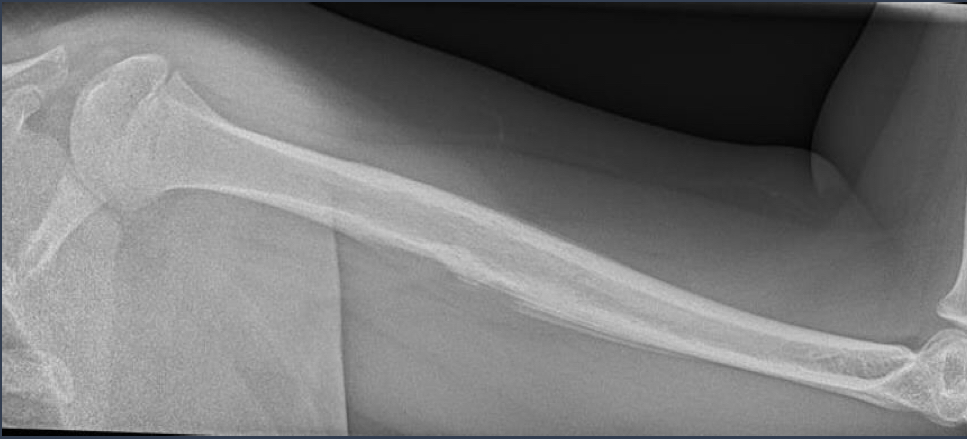

how do you describe this?

what does it point to?

blade of grass

paget disease